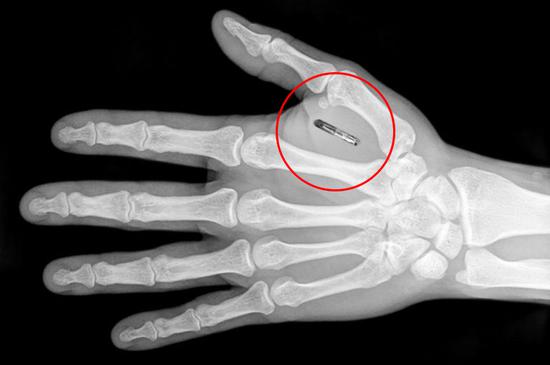

据描述,芯片的植入方式非常简单,芯片注射器会在拇指与食指之间移动,找准位置,然后像是点击鼠标一样“咔擦”一声,芯片就植入完毕了。

据了解,这种小型植入芯片使用的是近场通信(NFC)技术,与非接触式信用卡或移动支付相同。当距离芯片几厘米(或者几英寸)的读取器激活时,少量的数据通过电磁波在两个设备之间完成传递。被植入的芯片是“被动的”,意思是它们包含其他设备可以读取的信息,但不能自己读取信息。